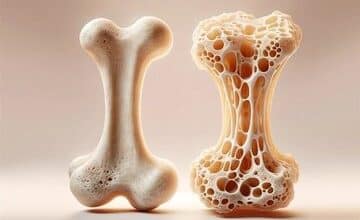

ویتامینی که برای سلامت استخوانها ضروری است

ویتامین A برای بینایی، سلامت پوست، سیستم ایمنی و سلامت استخوان ضروری است. به گزارش آرمان زنان ، مصرف زیاد…